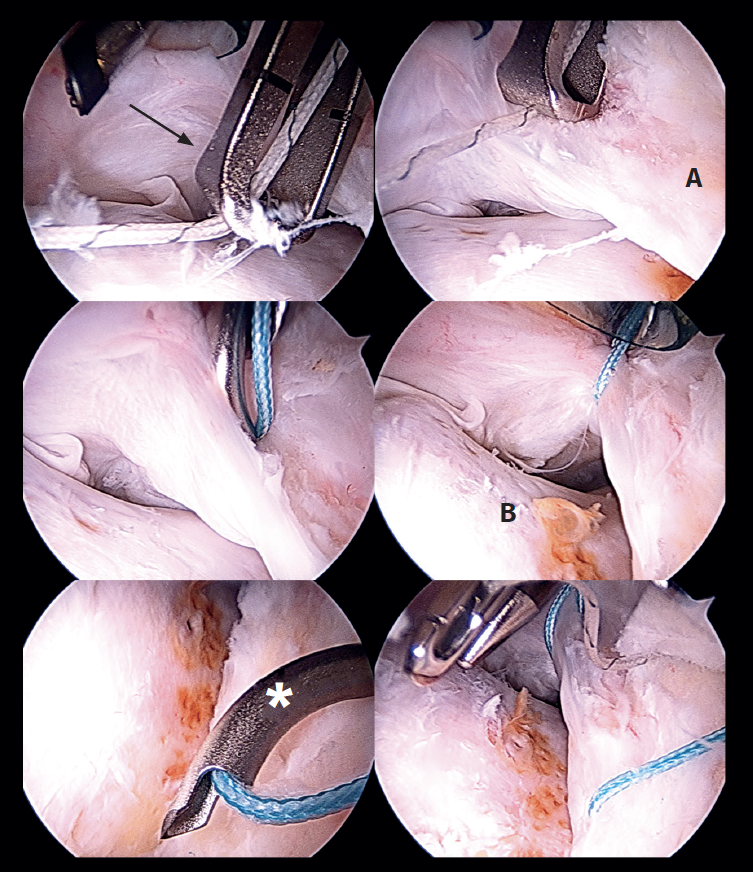

Capsular reconstruction procedure

Treatment of the capsule defect is carried out through capsular reconstruction using the modified kite technique described by Ellman(8). To perform this technique, we measure the dimensions of the proximal-distal capsule defect using the shoulder capsular reconstruction guide (Arthrex). It is important to measure the capsule defect in extension in order to avoid discordances. The last step in the preparation phase is to place two distal simple sutures in the native capsule using a SlingShot® (Stryker) suture passing device, and which will serve as a guide for the definitive sutures (Figure 8). The distal anterior suture is passed and reserved through the accessory DALA, and the distal posterior suture is passed and reserved through the DALA. Lastly, we prepare and cut an acellular dermal graft (Epiflex®) suited to the dimensions of the graft (in this case 2 x 2 cm). One of the extremities of the sutures of the anchorings previously placed at acetabular level and reserved in the proximal middle anterior portal (PMA) is extracted through the DALA and is passed through the proximal portion of the graft using Scorpion® (Arthrex) forceps. In the distal portion of the graft we also introduce FiberWire® number 2 sutures using Scorpion® forceps (Figure 9). Once the graft has been prepared, it is placed inside the joint and fixed at proximal level (Figure 10). Fixation of the distal portion of the capsule is then carried out. The point of this distal fixation is a soft tissue-to-soft tissue anastomosis in the zona orbicularis, which often marks the distal extent of the capsule defect according to most of the capsulectomy procedures. For this purpose we use the stitches previously placed and reserved in the accessory DALA and the DALA as a shuttle. Medial and lateral fixation to the capsule remains is then performed with FiberWire® number 2 stitches (Figure 11). The sutures are knotted with the hip in 10º flexion and neutral rotation. Finally, we check the stability of the graft through flexion and rotation movements. An illustration of the final result of the capsular reconstruction procedure and of the segmental labral reconstruction is shown (Figure 12).